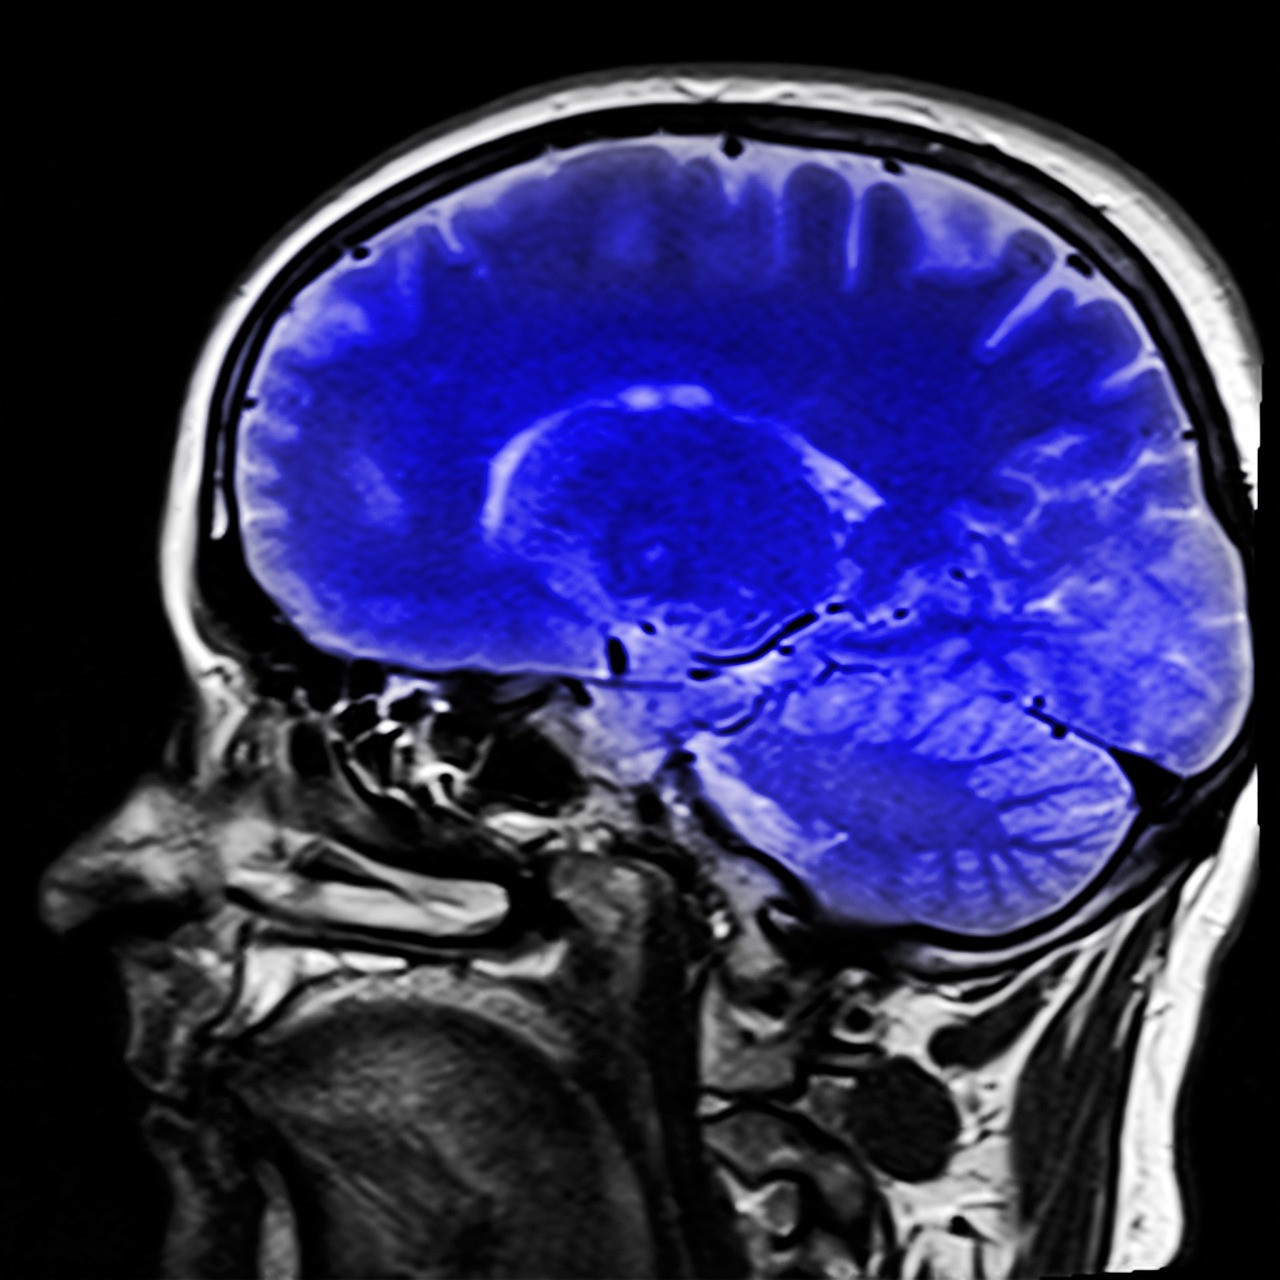

Lyme Disease and Its Effects on the Brain

While it can affect different parts of the body, it can also have a significant impact on the brain and central nervous system. In this article, we will discuss the effects of Lyme disease on the brain and how it can lead to various neurological symptoms.